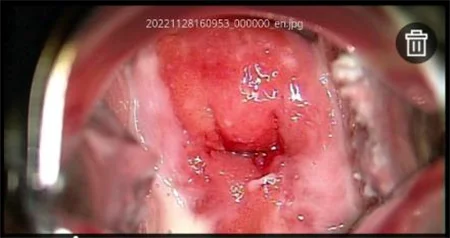

[ЗУРГИЙН ЦОМОГ]

Зүүн доод талд байгаа цомгийн товчлуур дээр дарахад та зургийн цомгийн дэлгэцийг харах болно. Зургийн цомгийн дэлгэцийн голд хамгийн сүүлд авсан зураг, доод мөрөнд өмнөх зургийн жагсаалт, хоёр талдаа хажуугийн цэс харагдана. Доод зургийн жагсаалтад зургуудыг авсан цагийн дарааллаар жагсааж харуулдаг. Дараагийн зургуудыг харахын тулд гүйлгэж харна уу! Цагаан өнгийн цэг нь таны одоо харж байгаа зургийг илэрхийлнэ.

Зураг 12 - Цомгийн дэлгэцийн харагдац